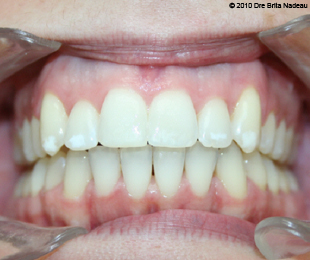

Marie-Hélène Cyr - Central intraoral view - After orthodontic treatments and orthognathic surgeries (January 29, 2010)

January 29, 2010 - My teeth when my orthodontist concluded that I was a finished case.